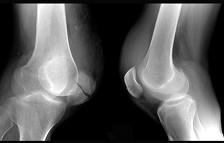

问题 引起图示横形骨折的病因多为 ( )

选项 A、病理性骨折 B、直接暴力 C、间接暴力 D、积累性劳损 E、肌肉的猛烈收缩

答案 E